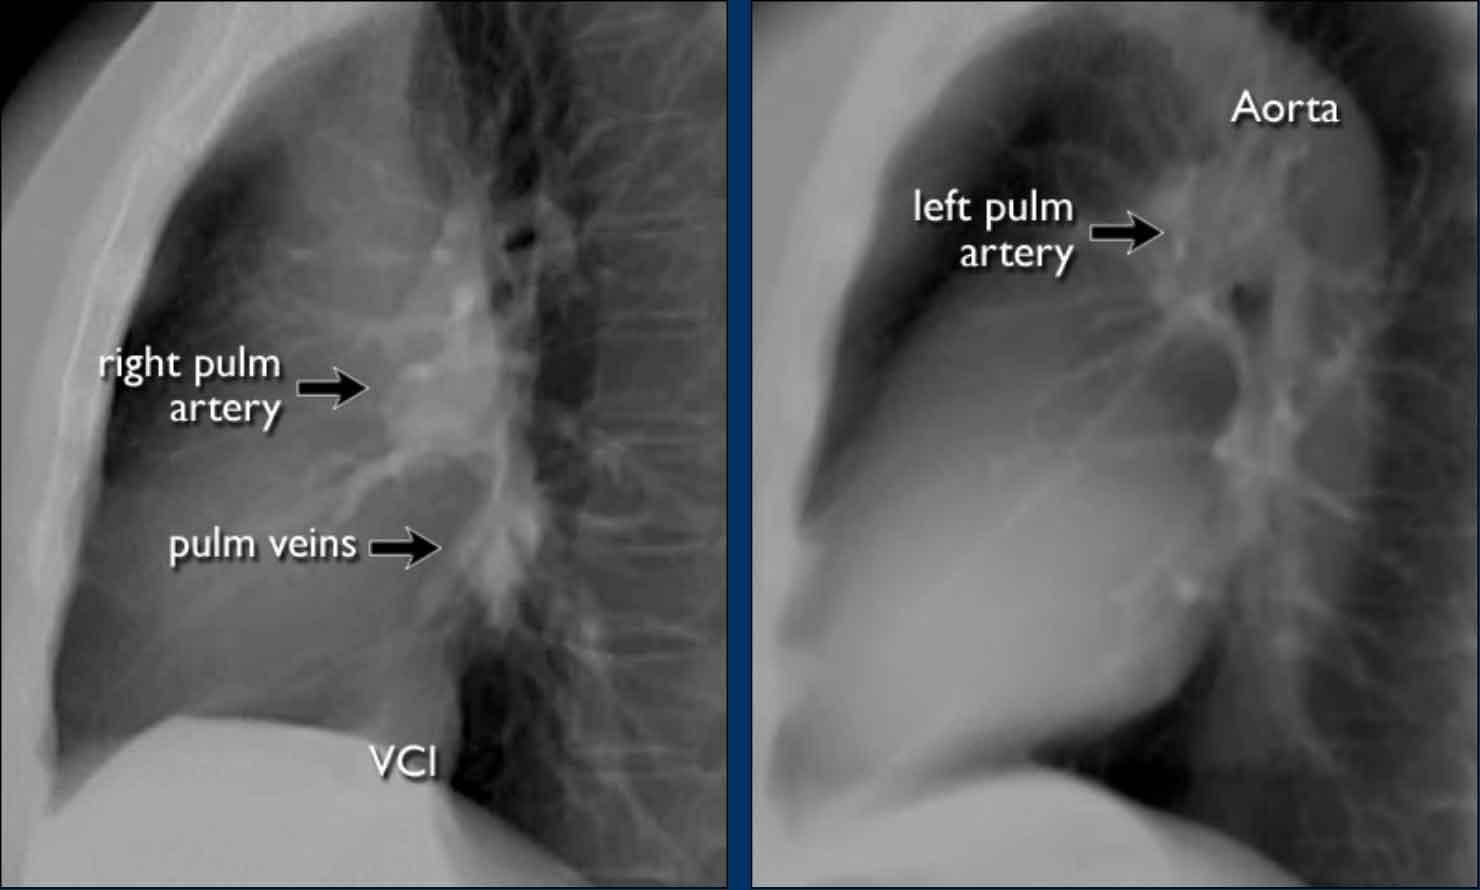

Tư thế nghiêng

Trên phim X-quang ngực tư thế nghiêng, các bờ tim cần được xác định rõ ràng, và tĩnh mạch chủ dưới (IVC) thường có thể thấy đổ vào nhĩ phải.

Mạch máu Phổi và Cấu trúc Rốn phổi

Động mạch phổi trái (màu tím) vòng cung phía trên phế quản gốc trái và nằm cao hơn động mạch phổi phải (màu xanh lam), động mạch này đi phía trước phế quản gốc phải.

Hiểu biết về giải phẫu rốn phổi bình thường trên tư thế nghiêng giúp phát hiện các bất thường.

Ví dụ:

- Trên tư thế PA, có thể nhận thấy rốn phổi to, nhưng khó phân biệt giữa giãn mạch máu và hạch to.

- Trên tư thế nghiêng, sự hiện diện của các đám mờ tròn ở những vùng mà mạch máu phổi bình thường không có mặt gợi ý mạnh mẽ đến hạch bạch huyết to.

Bờ Từng Buồng Tim trên Tư Thế Nghiêng

- Nhĩ Trái: Tạo thành bờ tim sau-trên; giãn gây phồng ra phía sau.

- Thất Trái: Tạo thành bờ tim sau-dưới; giãn gây di lệch ra sau-dưới.

- Thất Phải: Chiếm khoang sau xương ức phía dưới; giãn lấp đầy khoang sáng sau xương ức theo hướng từ dưới lên trên.

Một đặc điểm giải phẫu quan trọng cần lưu ý là rốn phổi trái bình thường nằm cao hơn rốn phổi phải.

Mối tương quan này xuất phát từ đường đi của các động mạch phổi: động mạch phổi trái vòng cung qua phía trên phế quản gốc trái, trong khi động mạch phổi phải đi phía trước phế quản gốc phải — vốn thường nằm thấp hơn phế quản gốc trái.

Các động mạch này có hướng đi thẳng đứng hơn so với các tĩnh mạch phổi, vốn chạy theo hướng nằm ngang hơn về phía nhĩ trái — nằm ở phía dưới so với mức các động mạch phổi chính.

Trên phim X-quang ngực tư thế nghiêng, cả động mạch và tĩnh mạch phổi đều có thể nhận diện được và không nên nhầm lẫn với hình ảnh hạch bạch huyết to. Đôi khi, các tĩnh mạch phổi có thể trông nổi bật hơn bình thường.

Động mạch phổi chính trái đi phía trên phế quản gốc trái và nằm cao hơn động mạch phổi phải — vốn đi phía trước phế quản gốc phải.

Các hình ảnh đính kèm là tái tạo CT lát cắt dày theo mặt phẳng sagittal của lồng ngực, giúp tăng cường khả năng hiển thị các cấu trúc rốn phổi.

Các động mạch phổi thùy dưới đi xuống từ rốn phổi theo hướng thẳng đứng.